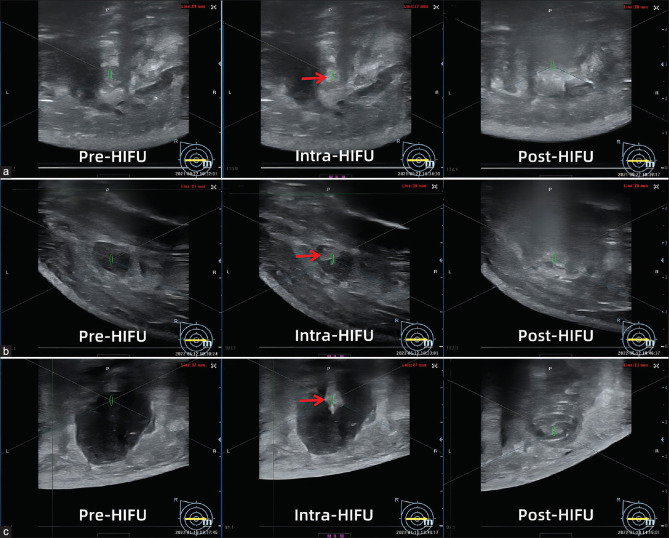

Materials and methods: A total of 88 patients with 245 lesions diagnosed with FA by core needle biopsy from January 2021 to November 2023 were included in this study. US-guided HIFU was performed under local anesthesia. Baseline and treatment characteristics were recorded and analyzed. FAs were divided into three groups according to the longest diameter for further analysis. After the treatment, follow-up with volume evaluation and physical examination was performed at 3, 6, and 12 months.

Results: There were 56 FAs ≤10 mm (group 1), 144 FAs with a diameter of 10-20 mm (Group 2), and 45 FAs of 20-30 mm (Group 3). The sonication time of the three groups was 22.5 s, 45.0 s, and 83.0 s (P < 0.05). Based on contrast-enhanced ultrasound evaluation, the median nonperfused volume ratio of the three groups was 74.1%, 87.6%, and 79.2% (P > 0.05), respectively. The volume reduction rates (VRR) of the three groups were 47.3%, 77.0%, and 82.0% at 12 months after HIFU, showing statistical differences. All patients were tolerated well and there were no adverse events after HIFU.